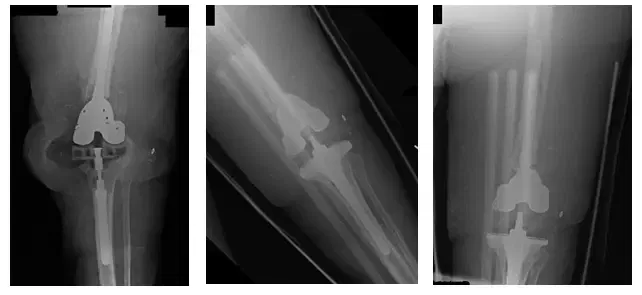

El paciente es un varón de 85 años que se presentó con una prótesis tumoral de rodilla izquierda luxada. El paciente llevaba 3 meses en el postoperatorio de una artroplastia total de rodilla (ATC ) con tumor izquierdo Reconstrucción. El paciente requirió cirugía para...